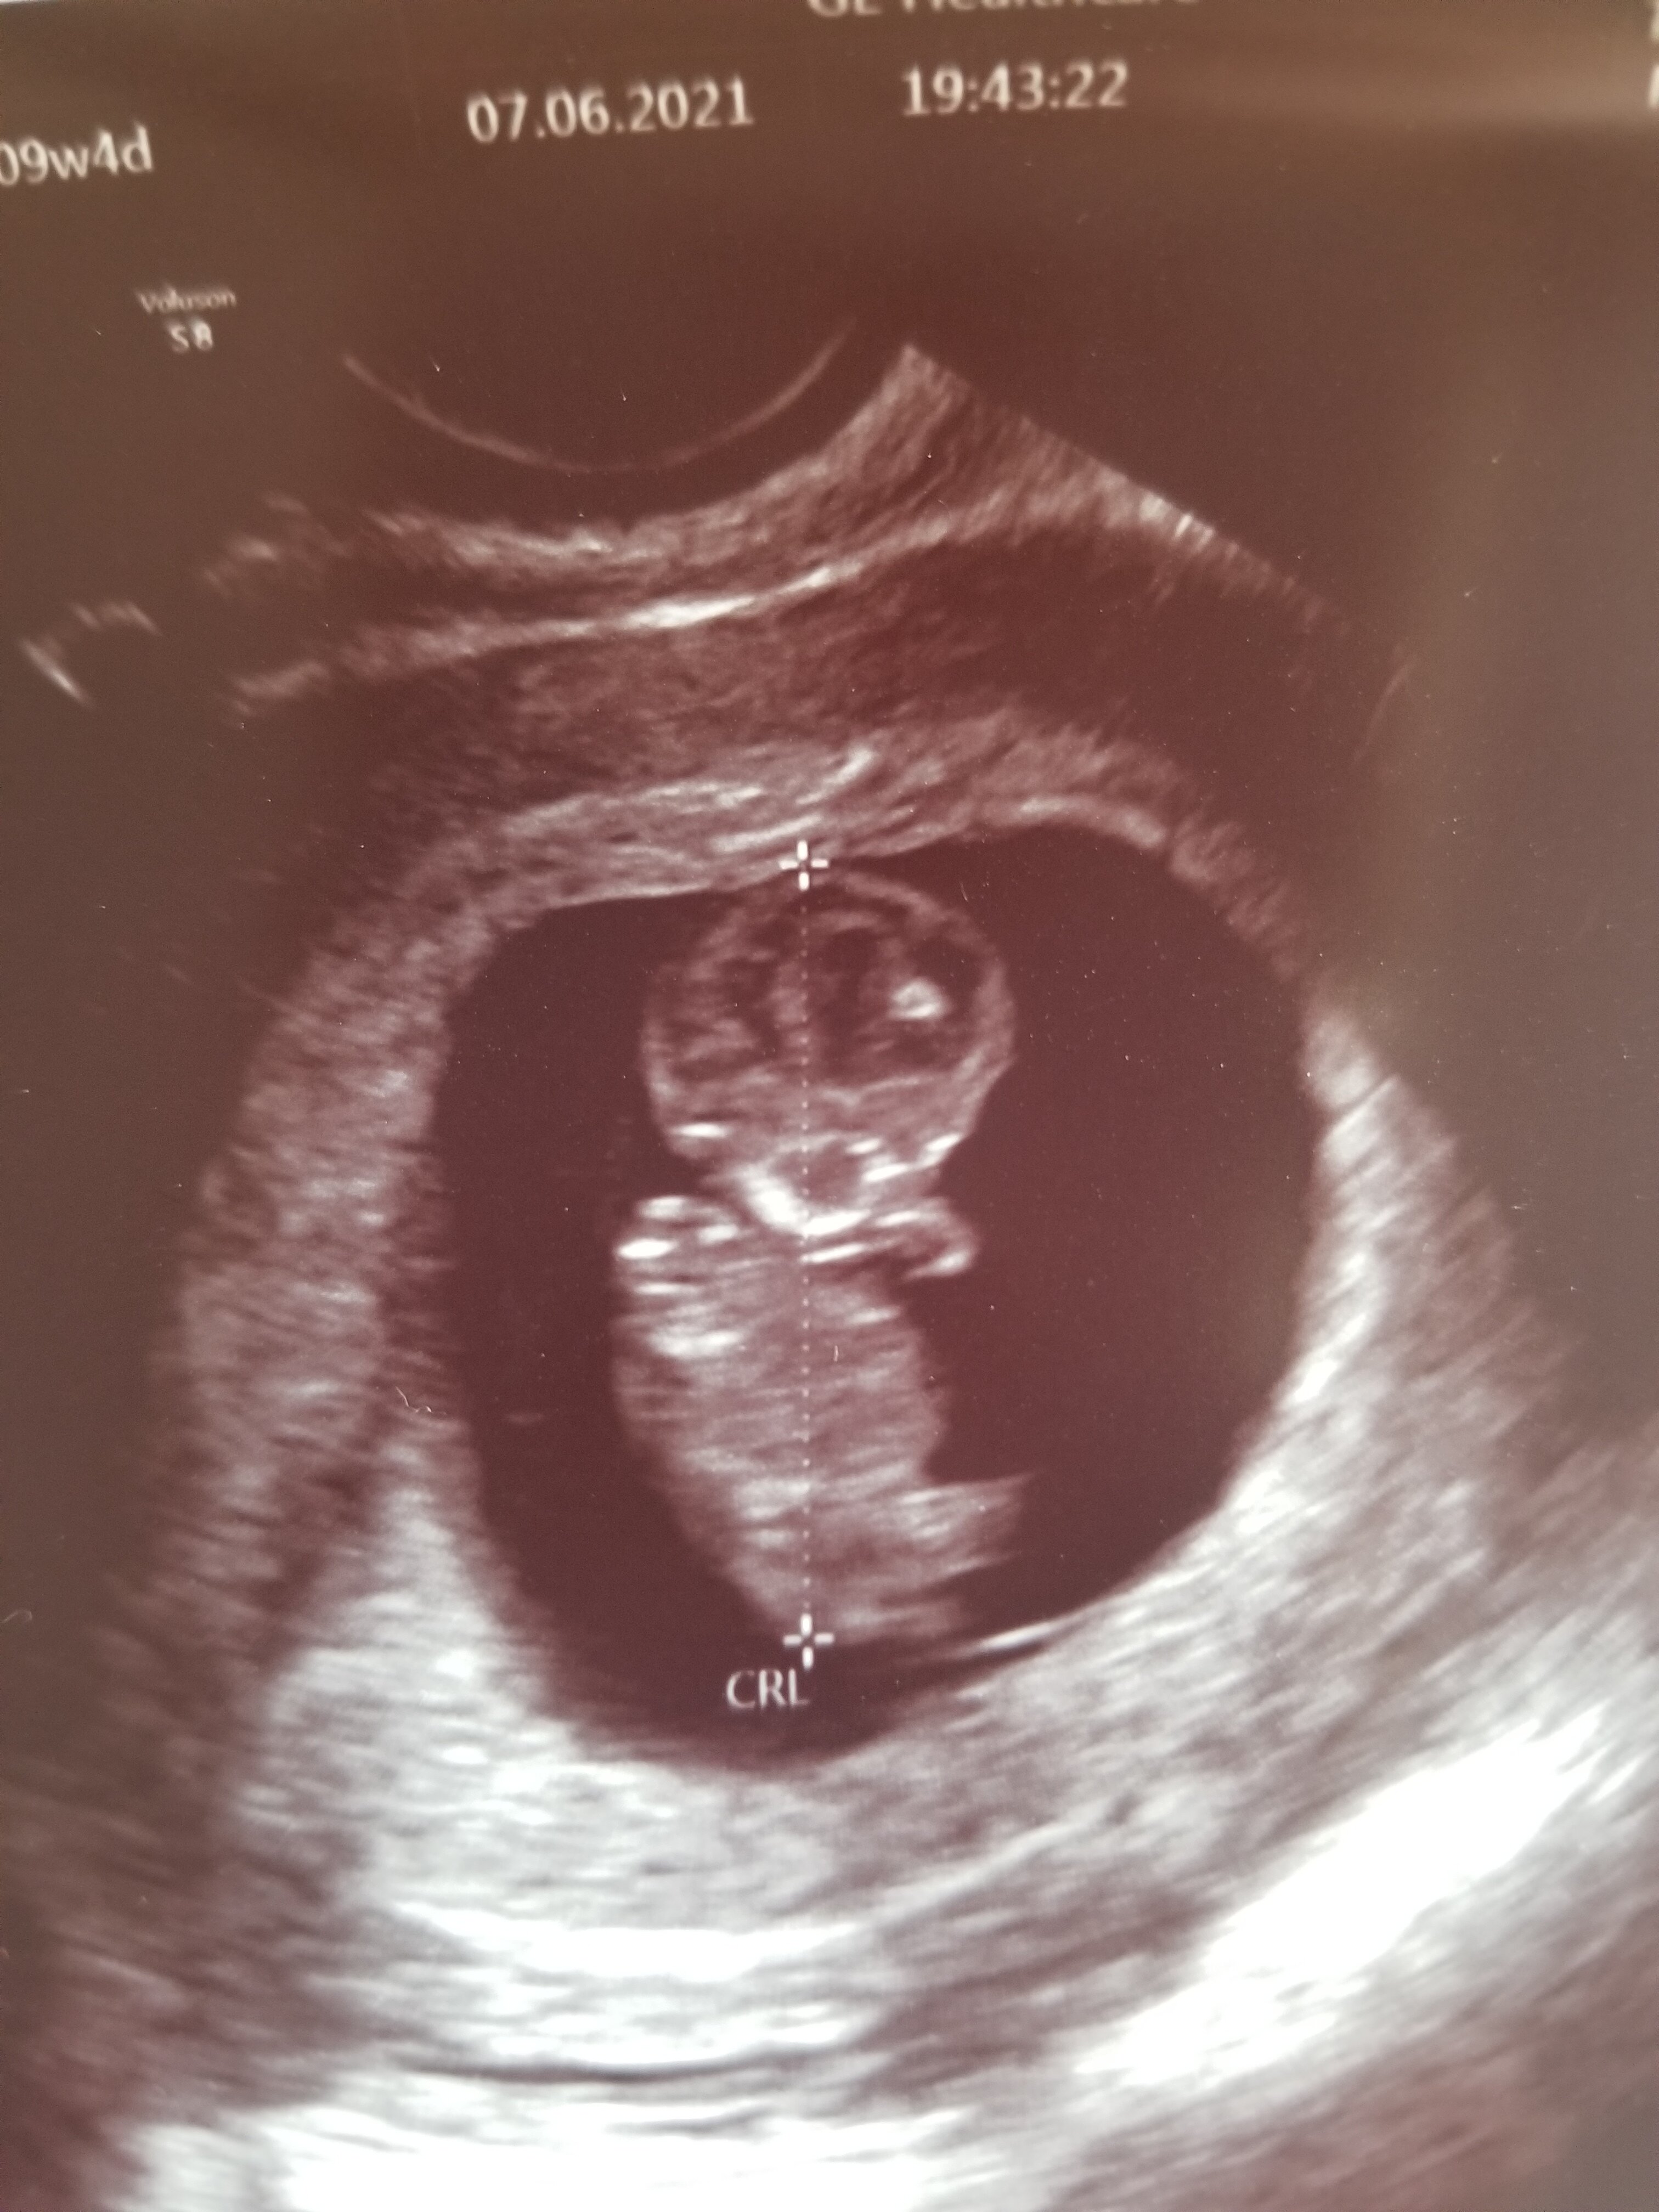

Czytam Was od początku, ale dopiero teraz się odzywam, bo strach że może coś pójść nie tak jak ostatnio ( w zeszłym roku) jest nadal ogromy. Po wczorajszej wizycie końcówka 10tyg. Proszę trzymajcie kciuki żeby teraz już wszystko było dobrze. Dzidziuś rośnie. Załączam zdjecie, wita się z ciociami :)

Termin aktualnie na 7.01 :)

Załączniki

• 0957EEFA-83E0-4130-A3FF-37AD1A039B36.jpeg

0957EEFA-83E0-4130-A3FF-37AD1A039B36.jpeg

1,1 MB · Wyświetleń: 136